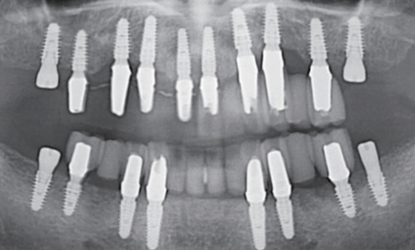

Implantų pozicionavimas ir restauracijų modeliavimas toleruoja ne didesnę nei 1mm paklaidą

Implantų pozicijos ir galutinės restauracijos toleruoja ne didesnę nei 1mm paklaidą, taip užtikrindamos puikią estetiką ir funkciją.

Netiksliai pozicionuoti implantai praranda galimybę atlaikyti okliuzines jėgas, todėl netiksliai pozicionuoti implantai dažniausiai kenčia nuo periimplantitų, kuris būtent sąlygoja trumpesnį implantų ilgaamžiškumą

Implantai įsriegti pagal suplanuotą protokolą

Restauracijos uždėtos pagal suplanuotą protokolą